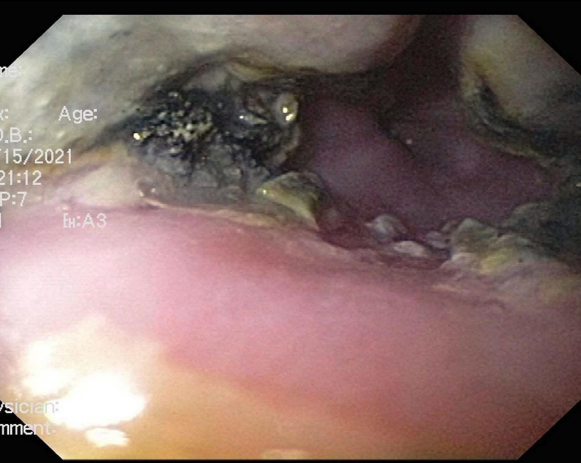

The patient was prepped and draped in a sterile fashion. Access was obtained under ultrasound and fluoroscopic guidance. A working access point was achieved in the right femoral artery and additional catheters were placed in the left common femoral artery, and in an antegrade direction in the left superficial femoral artery. The right internal jugular vein and right femoral veins were similarly accessed. This is standard practice in our catheterization laboratory in high-risk cases to facilitate expeditious percutaneous extracorporeal membrane oxygenation (ECMO) cannulation in the event of cardiovascular collapse. Biplane angiography was performed before placing a guide wire with its tip in the right subclavian artery and upsizing the access sheath for a 12 French 65 cm long sheath (Figure 3A). At this point, the pre-procedural CT imaging that had been post-processed using Philips © VesselNav software (Image Z) was overlayed for live procedural guidance. The landing zone for the stent had been marked on the 3D CT dataset to ensure coverage of the zone of evolving aorta-enteric communication (Figure 3B). A 34 mm long covered stent along with a 36 mm uncovered stent were piggyback mounted on a balloon. The balloon stent complex was inserted to the intended position using fluoroscopic live overlay guidance. The inner and outer balloons were inflated using single inflations after which the balloon was removed over the wire and an additional balloon was inserted and inflated with good stent expansion on fluoroscopy. Pullback pressures documented no gradient across the stent. The catheter was removed, and post intervention angiography was performed demonstrating a satisfactory result (Figure 3C). Local anesthetic was given, and the sheaths were removed. The patient was extubated and transferred to the cardiac intensive care unit for further management. The total procedural time was 89 minutes and total blood loss was twenty milliliters.

Figure 3: Panel A demonstrates a single plane aortic angiogram with a pigtail catheter in the aortic arch. There is no evidence of descending thoracic aortic luminal interruption at the level of the gastro- esophageal junction.

Panel B demonstrates live overlay of the 3D CT imaging with a ring landmark (green) in place at the intended zone of stent deployment. There is a stent partially expanded on the fluoroscopic image in the intended landing zone.

Panel C demonstrates a still frame from a 3D rotational angiogram demonstrating satisfactory expansion of a stent complex within the intended landing zone in the descending thoracic aorta.

Figure 3